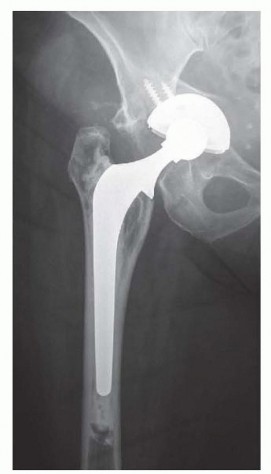

DEFINITION Total hip arthroplasty (THA) is the standard of care for symptomatic degenerative joint disease (D…

Introduction Total hip arthroplasty can provide predictable pain relief and improve function in patients with…